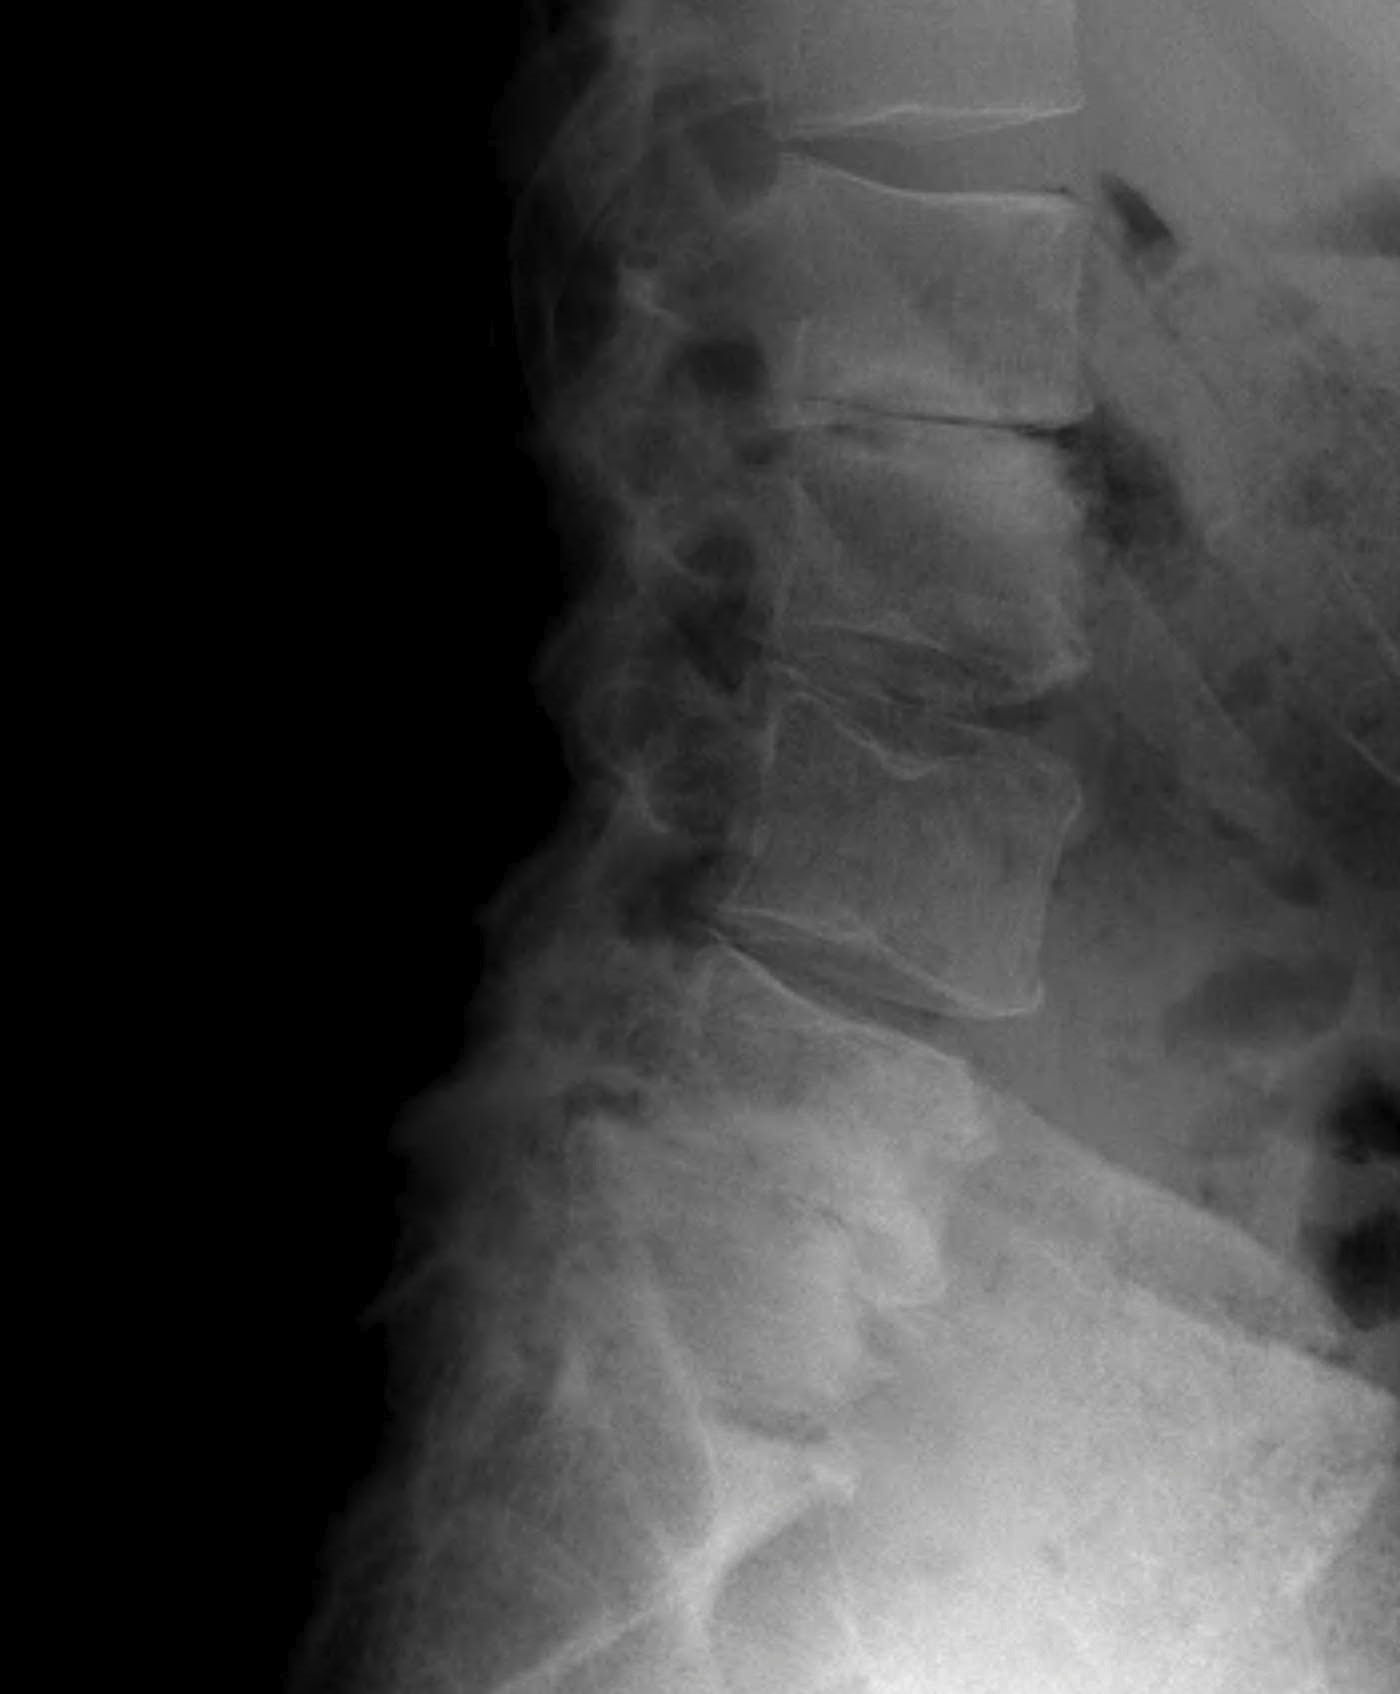

X-ray

Disc degeneration

- disc space narrowing

- vertebral sclerosis

- osteophytes